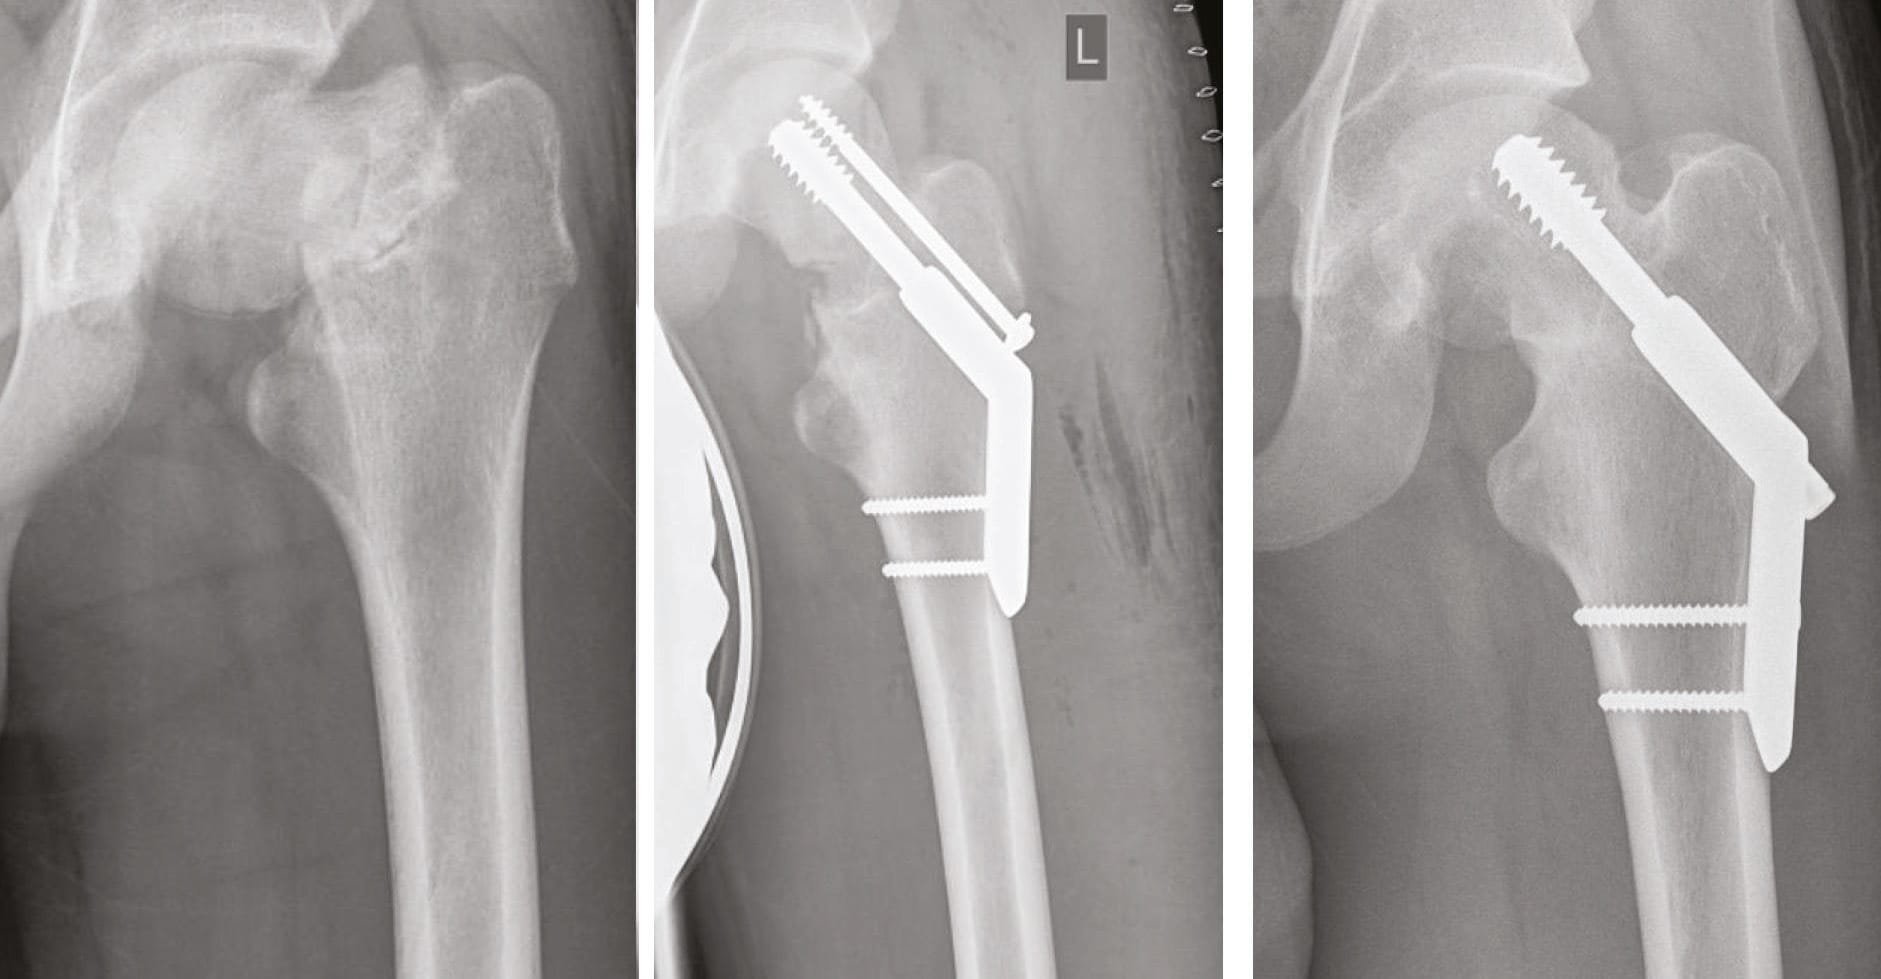

However, in younger patients joint restoration is still the gold standard (Figure 1) and should be favoured.

- Intra-operative findings: structure of cortical ring (Figure 1), bone quality during reaming process.

Conservative treatment remains an option, but only a small number of patients are eligible. Secondary dislocation can occur in up to 50% (Figure 3). In younger patients (<65 years) osteosynthesis with a DHS is our preferred method (Figure 2). In patients >65 years we prefer joint replacement even in undisplaced fractures (Garden I + II). Therefore the majority of our cases is treated with joint replacement procedures (Table 1.).

Hemiarthroplasty (HA) with 37% is still widely used. However, 57% of our patients obtain a THA. Cemented fixation is necessary in most cases due to bone quality, intraoperative cortical ring structure or known osteoporosis in the patient history. In active patients with good bone quality, femoral Dorr type A or B, intact cortical ring cementless fixation is possible. If cementless fixation is considered short stem fixation is possible and our favoured method. Straight cementless stems are rarely used. Our clinical and radiographic results using cementless short stems so far are very promising (Figure 4). Clinical results in these selected cases are excellent and complication rates are low. Currently a clinical and radiographic study is under process and will be finished by 2019.